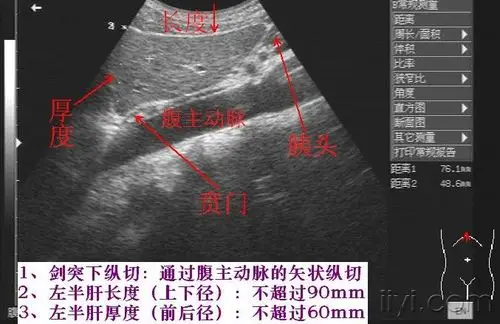

肝脏实习内容图片集